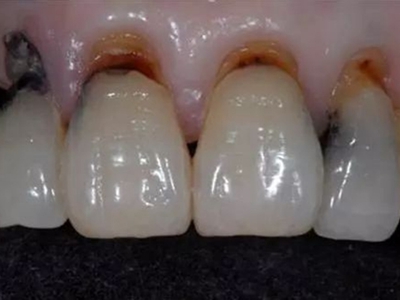

楔状缺损是一种非龋性牙颈部慢性损伤,是指发生在牙齿唇、颊面颈部的慢性硬组织缺损。典型缺损由两个夹面组成,口大底小,呈楔形。楔状缺损多发生于中老年人,主要原因是刷牙不当,防治措施是调整咬合关系,改善刷牙方法,配合相应的治疗。

楔状缺损与年龄相关,即年龄越大,缺损越重,患者多有横刷牙习惯,患牙为多颗甚至全口,常以口角附近的牙齿(尖牙、前磨牙)为重。典型表现为牙颈部缺损,呈楔形,由两个夹面组成,口大底小,缺损处质地坚硬,表面光滑,边缘整齐,无染色,轻微泛黄常为牙齿本色,严重时可导致牙髓腔暴露甚至牙齿横向折断,根据缺损深浅不同,可伴有牙齿敏感甚至疼痛。